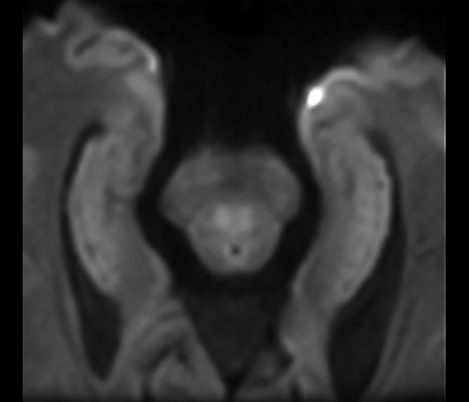

El 70% de los radiólogos consideran que las indicaciones neurológicas son un desafío, sobre todo debido a la falta de técnicas apropiadas de imagenología y visualización¹. Philips tiene como objetivo proporcionar la mejor claridad de diagnóstico posible y orientación terapéutica para todos los pacientes con trastornos neurológicos. Al aprovechar nuestra plataforma digital dStream, este año presentamos un conjunto de estrategias nuevas de imagenología y visualización. Esto puede ayudarlo a resolver preguntas sobre neurología complejas con mayor certeza, así como a desbloquear nuevos territorios neurológicos en aplicaciones neurofuncionales avanzadas. Este es un paso clave para aumentar el diagnóstico neurológico y, en última instancia, impactar más vidas con la RM. ¹ TMTG Market Survey 2016